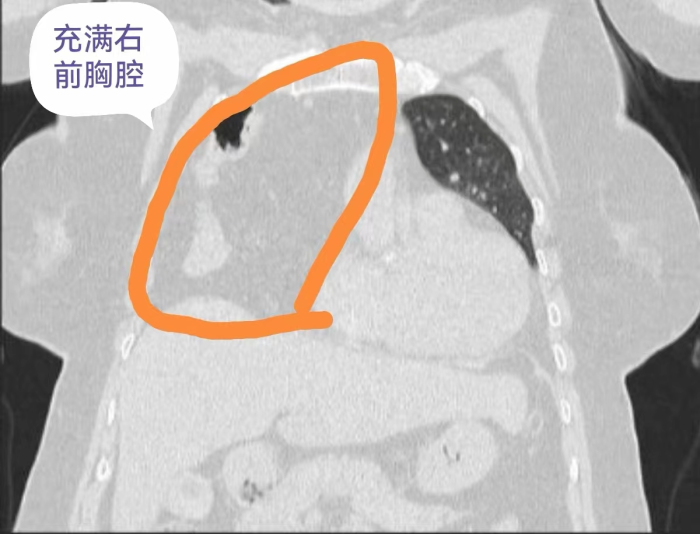

近日,刘奶奶(75岁)来到贵州航天医院做了胸部CT、冠脉造影等检查,经过心血管内科、呼吸与危重症医学科、心胸外科、影像科等多学科会诊讨论,确诊并没有冠心病,而是因为有“膈疝”导致她的一系列症状。而且,刘奶奶的膈疝还非常严重,腹部的肠管和网膜已经“跑”到右侧胸腔顶部去了,还占据了整个右侧前胸腔,难怪会出现那么明显的症状。通常这类严重的膈疝多采用开放手术,需要至少15厘米长的切口。